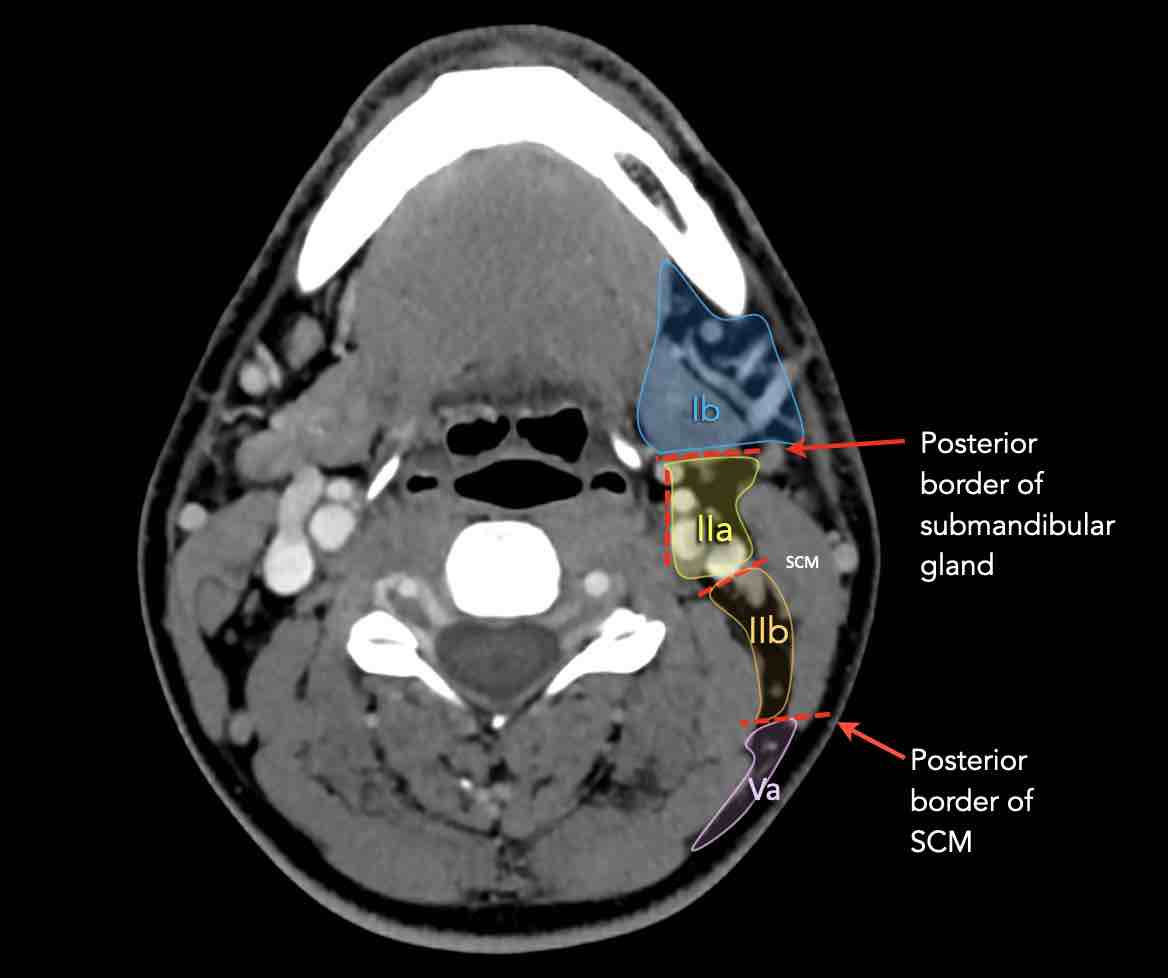

Tầng II có thể được chia thành tầng IIa và tầng IIb bằng cách vẽ một đường tại bờ sau của tĩnh mạch cảnh trong.

Các hạch bạch huyết ở tầng IIa và IIb có nguy cơ chứa di căn từ các ung thư hốc mũi và khoang miệng, vòm hầu, hầu miệng, hạ hầu, thanh quản và các tuyến nước bọt lớn.

V – Tam giác cổ sau và hố thượng đòn

Tầng V chứa các hạch của nhóm tam giác cổ sau nằm ở phía sau cơ ức đòn chũm, xung quanh phần dưới của thần kinh phụ gai sống và các mạch máu cổ ngang.

Các hạch bạch huyết ở tầng V thường liên quan nhất đến các ung thư nguyên phát của vòm hầu, hầu miệng, các cấu trúc da vùng da đầu phía sau và tuyến giáp.